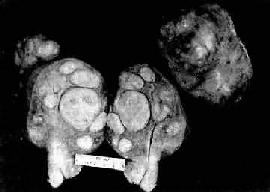

三、子宫肿瘤(一)子宫平滑肌瘤 子宫平滑肌瘤(leiomyoma)是女性生殖器官中最常见的一种良性肿瘤,多见于30~50岁妇女,20岁以下罕见,绝经后肌瘤可逐渐萎缩。其发生可能与过度的雌激素刺激有关。临床上多数患者可无症状,若出现症状,则表现为月经过多及局部肿块等。 【病变】 肉眼观,肌瘤可以生长在子宫任何部位,常位于子宫壁内(肌层内肌瘤)、浆膜下(浆膜下肌瘤)或粘膜下(粘膜下肌瘤)。可单发或多发,常为多个,其数目多少不等,常见为数个、乃至十数个或数十个,称多发性平滑肌瘤。肌瘤的大小可极为悬殊,小的在显微镜下才可检见,大的如成人拳大或更大,甚至可充满整个腹腔。肌瘤多呈球形或融合成不规则形,质较硬,界限明显,但无明显包膜(图13-7)。切面上,瘤组织常呈灰白色,编织状或旋涡状,当肌瘤生长较快或供血不足时,可发生各种继发性改变,如玻璃样变、粘液变、囊性变、水肿及出血、坏死等。

图13-7 子宫平滑肌瘤 多个肌瘤结节,位于肌壁内、粘膜下及浆膜下,境界分明,宫腔受挤压呈裂隙状 镜下,瘤细胞与正常子宫平滑肌细胞相似,但肌瘤细胞核比较密集,常排列成纵横交错的不规则束状或成编织状。核大多呈长杆状、两端钝圆或圆锥形,染色质纤细。肌细胞间有不等量的结缔组织。每10个高倍(400倍)视野核分裂像少于5个者一般为良性。有少数病例瘤细胞核增多、致密,核大活跃,染色质粗,无核分裂像,称细胞性平滑肌瘤(cellular leiomyoma)。子宫平滑肌瘤的恶变率很低,据报道为0.2%~0.5%,多见于年龄较大、生长较快与较大的肌瘤。如果核分裂像每个高倍视野达10个以上或有肌层及血管浸润者应诊断平滑肌肉瘤。 (二)子宫体癌 子宫体癌又称子宫内膜癌(carcinoma of endometrium),较常见,占女性生殖道恶性肿瘤的20%~30%。近年来子宫体癌的发病率有上升趋势。多发生在50岁以上绝经期和绝经期后妇女。病因未明,一般认为与雌激素长期持续作用有关。主要临床表现为不规则阴道流血。 【病变】 肉眼观,分弥漫型及局限型两种。弥漫型的子宫内膜呈弥漫增厚,不规则形、息肉或菜花状,质脆,常见出血、坏死或溃疡形成。癌组织浸润肌层,深浅不一(图13-8)。局限型多位于宫底或宫角,后壁多于前壁,常呈息肉状伴肌层浸润。